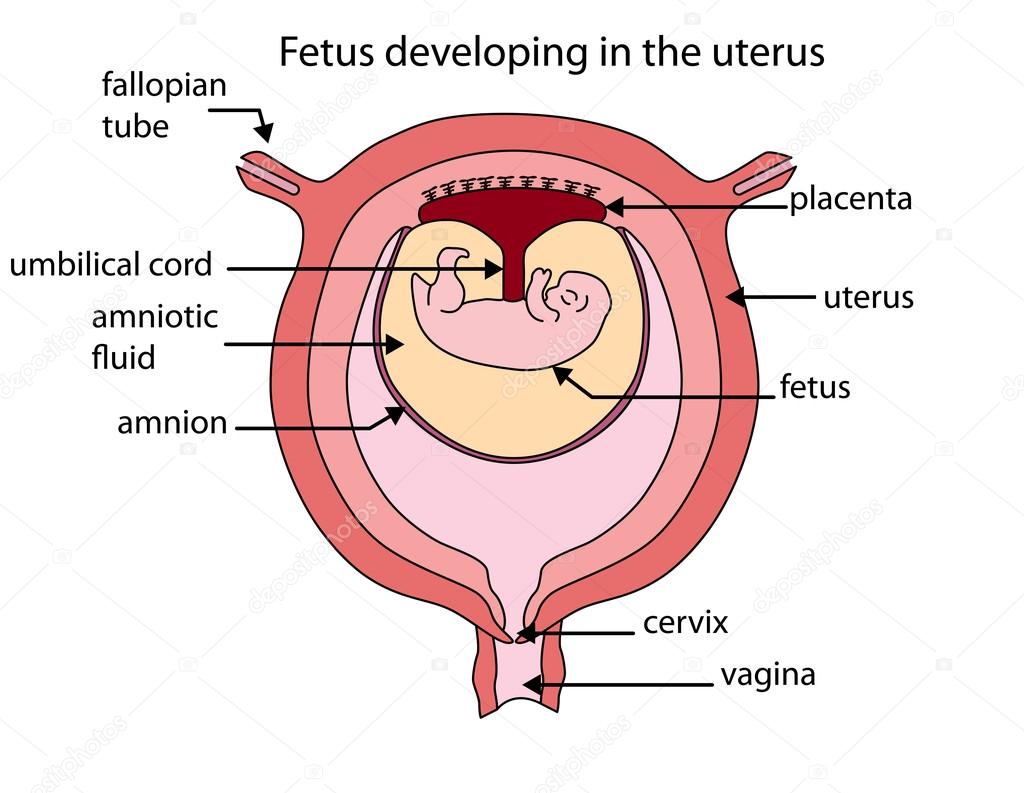

Fully Labeled Diagram Of Fetus Developing In The Uterus Stock

https://st2.depositphotos.com/1293234/8821/v/950/depositphotos_88210764-stock-illustration-fully-labeled-diagram-of-fetus.jpg